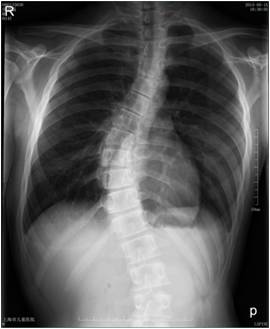

脊柱侧弯是脊柱最常见的畸形之一,是由脊柱节段中的一个或者多个向侧方弯曲同时伴有椎体旋转的空间三维畸形。(你可以理解为直的铁丝发生扭曲)

脊柱侧弯早起症状不明显,大部分都是到出现明显身体畸形,变成驼背时才被发现。主要的临床表现有站立时姿态不对称,双肩不等高,弯腰时背部不对称。严重者会出现胸廓旋转畸形,表现为两侧乳房不对称,上身倾斜,躯干缩短等。

如未能及时发现或处理,部分患者脊柱侧弯会逐渐加重而导致明显畸形,严重的不仅会造成身体外观异常、脊柱运动功能障碍或骨盆倾斜后的跛行,还可因胸廓畸形而造成心、肺功能障碍,其中大部分患者存在急性或经常性的慢性腰痛。【1月8日中华小弯针 • 全程医院临床带教】专业诊治颈腰椎、膝关节、股骨头坏死、强脊炎、三叉神经等疼痛及疑难杂症技术研修班